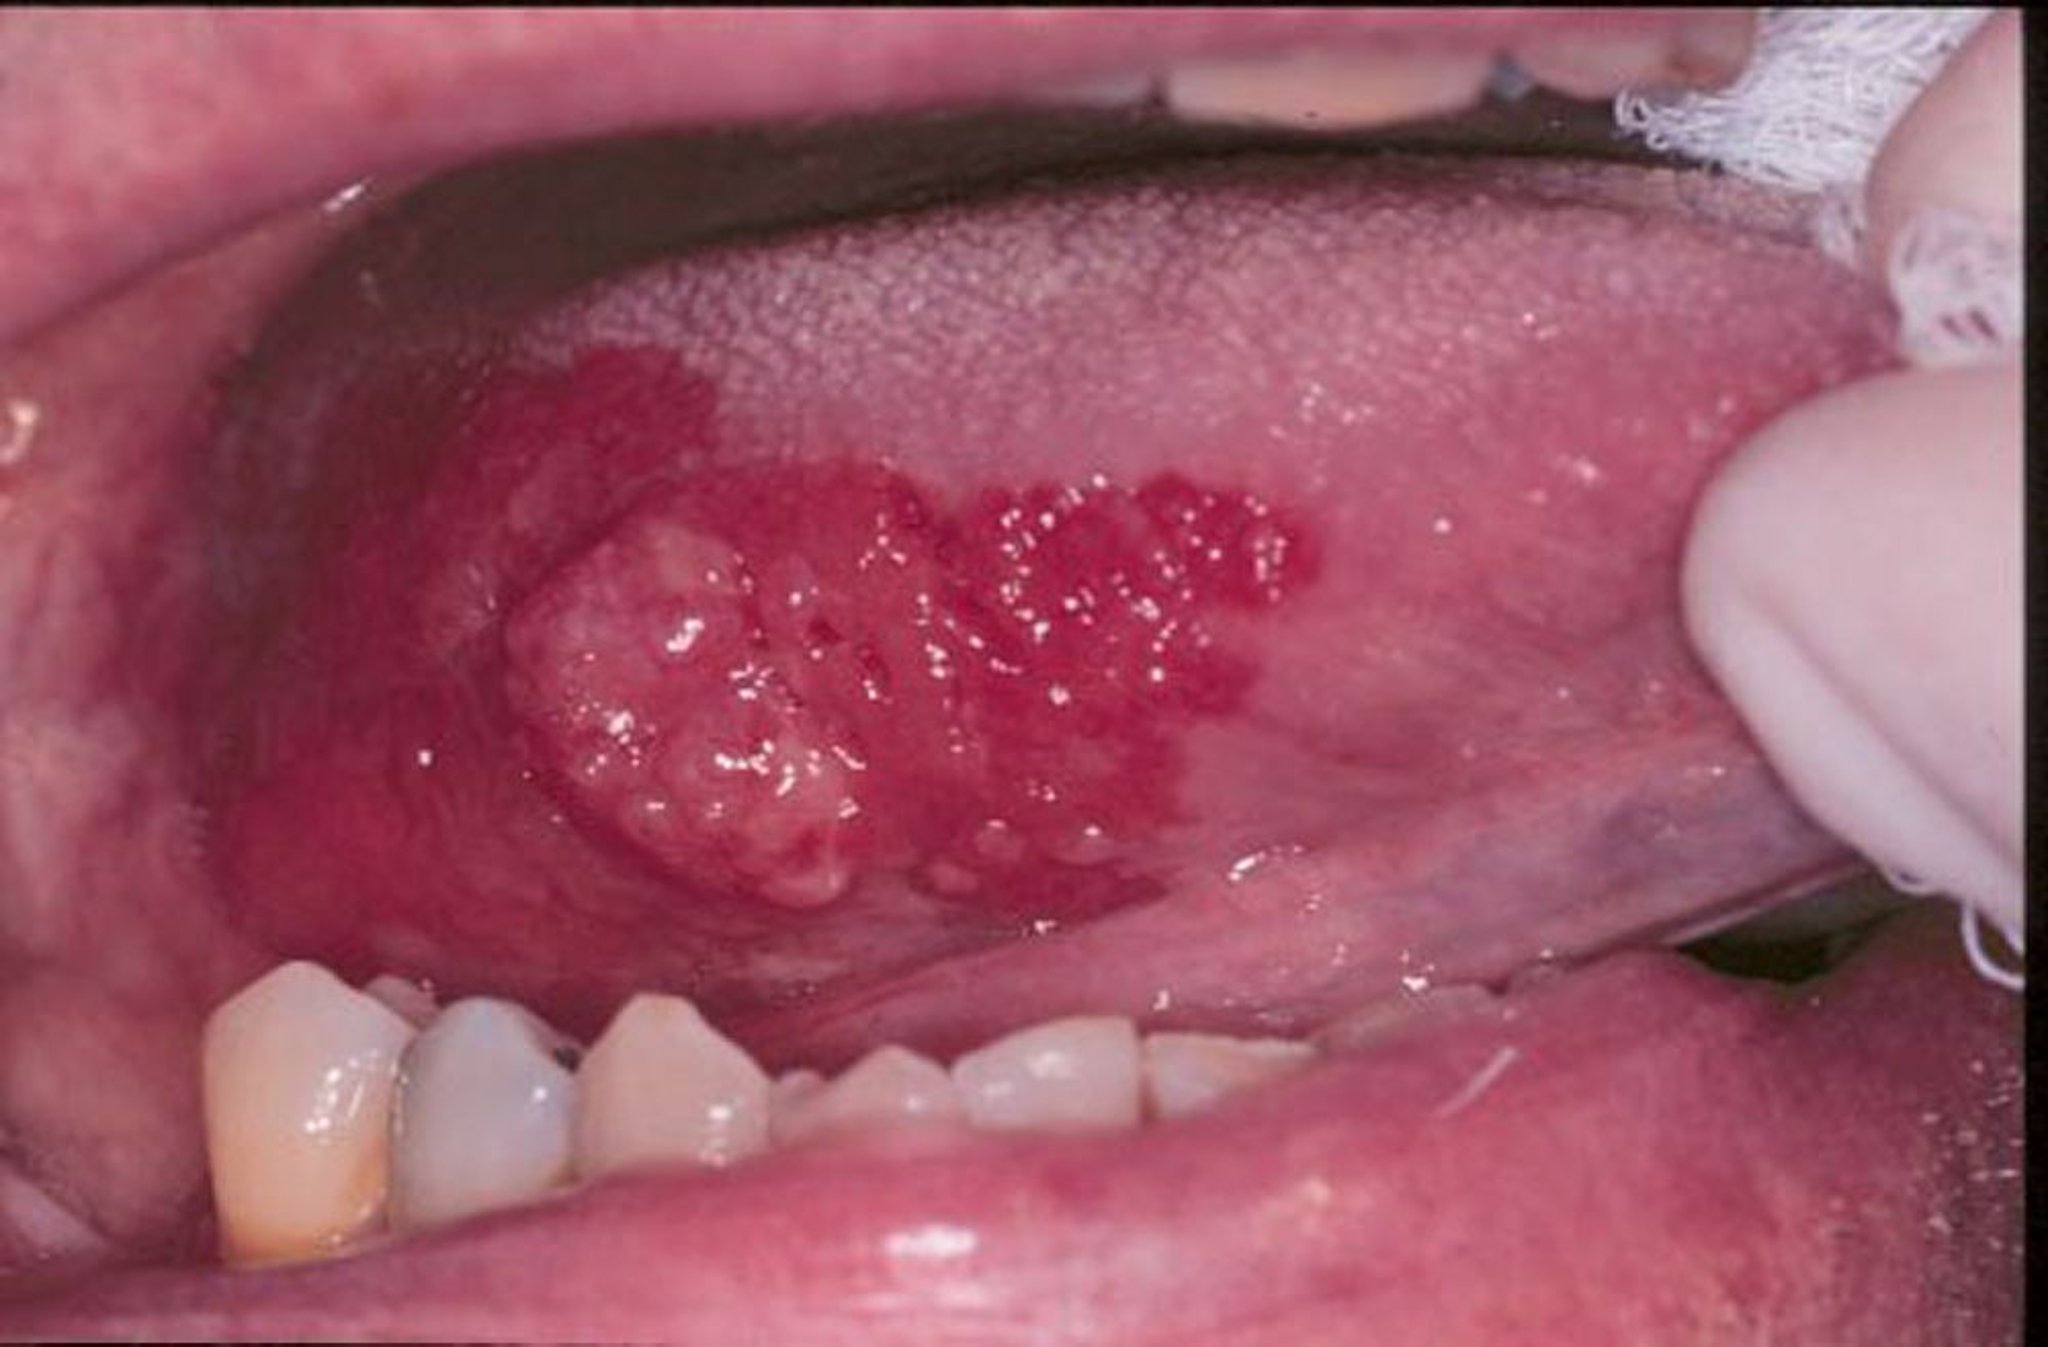

紅板症と扁平上皮がん

紅板症とは、口にできる赤い、平坦な、またはすり減った、ビロード状のただれを総称する用語です。この画像では、扁平上皮がんが紅板症の縁で取り囲まれています。

Image provided by Jonathan A.Ship, DMD.